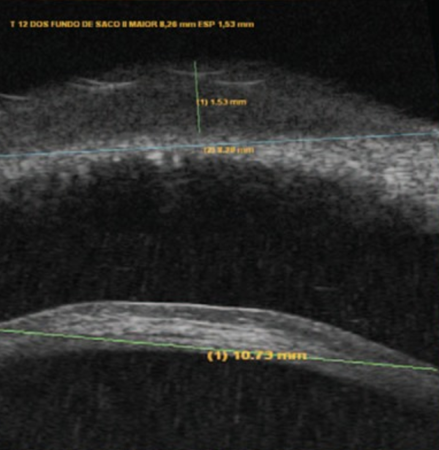

Figure 2. Ultrasound biomicroscopy of lesion depth (1.53 mm) and large diameter (10.73 mm).[7] Open access under terms of the Creative Commons License: http://creativecommons.org/licenses/by/4.0/. Original figures available at: https://eandv.biomedcentral.com/articles/10.1186/s40662-019-0151-4.